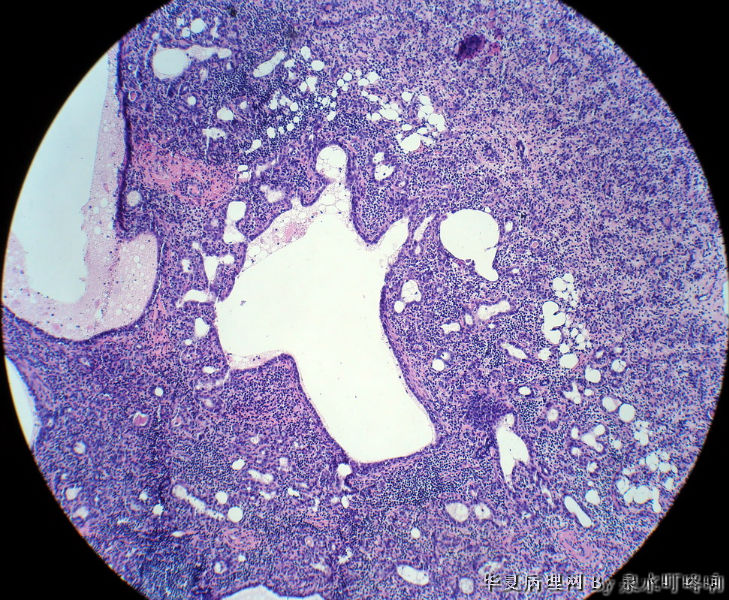

120213,女,23岁,右乳腺肿物半年,术中见肿物为多房性囊性肿物,内容黄色粘稠液体。

大体:灰白囊性肿物一个,大小约3×2×1.9厘米,局部囊壁增厚。

低倍小叶结构存在,炎细胞,导管扩张=炎症,考虑导管扩张症。

1.图像中有囊性增生,2.有腺病的结构,3.同时在低倍中可以看到有瘤样的结构,高倍中以腺肌上皮增生为主,未见核分裂,也未见恶性的现象,因此诊断乳腺的腺病瘤更为合适。

淋巴细胞性乳腺炎并导管扩张性囊性变。

乳腺小叶炎症导致小叶结构发生变形,有的腺泡萎缩,有的导管扩张,间质内淋巴细胞、纤维组织增生,都是炎症性适应性病变。